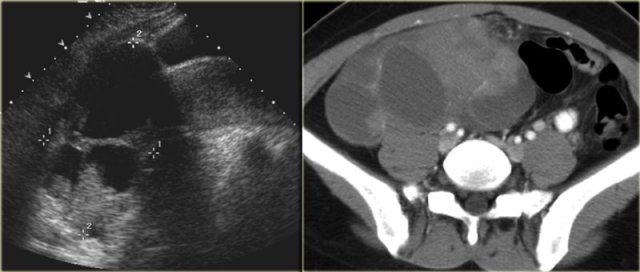

The ultrasound images show the right and left ovary: on both sides there is what appears to be a solid lesion.

There is however good through transmission, which indicates that we are probably dealing with hemorrhagic cysts.

On Doppler US (not shown) there was no vascularity.

Continue with the MR examination.

On an axial T1-weighted image both lesions are bright indicating fat, blood or high protein fluid.

Fat saturation does not suppress the signal in these lesions.

In an image with overall reasonably good fat suppression this rules out a fat-containing teratoma and confirms the suggestion of hemorrhagic fluid.

On the axial T2-weighted image both lesions show typical 'shading'.

The gradual drop in T2 is thought to be caused by a combination of increasing viscosity and increasing concentration of protein and iron towards the dependent portion of the lesion.

There is no enhancement on the subtraction image (Post-Gd minus Pre-Gd).

Again, subtraction is useful in cases like this: Gd-induced signal increase over the already very bright pre-contrast image would be very hard to appreciate otherwise.